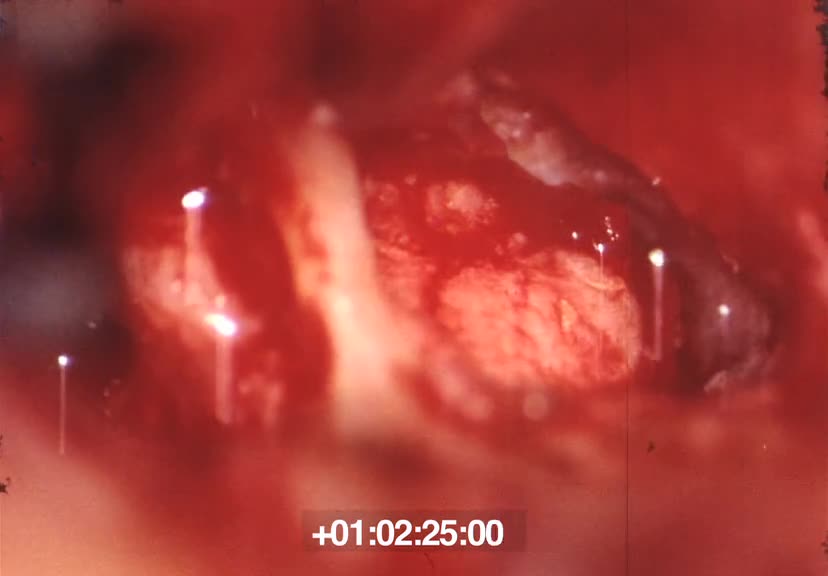

Film sur une opération chirurgicale, filmée en très gros plan. On y voit l'action des outils du chirurgien (bistouris, pinces, etc.) sur des organes du corps humain : nettoyage, incisions, etc. ...